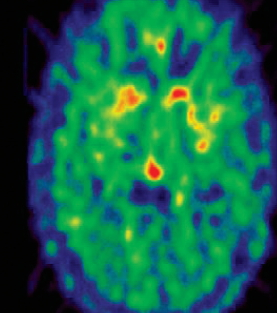

파킨슨병은 도파민계 신경이 파괴됨으로써 움직임에 장애가 나타나는 질환을 말합니다. 도파민은 우리가 몸을 정교하게 움직일 수 있도록 하는 중요한 신경전달 물질로 도파민계 신경이 60 ~ 80% 정도 소실되면 파킨슨병의 증상이 발현합니다.

정확하게 밝혀진 원인은 없지만 여러 가지 추측들이 있습니다. 파킨슨병은 70대 이상에서 80% 이상 발생하는 만큼 뇌 세포가 죽으면서 퇴행성으로 발생하는 질환으로 연구됩니다. 환경적인 요인 , 유전적인 요인 , 노화 등등 근본적인 원인은 없지만 뇌에 있는 도파민 신경세포가 감소하면서 운동 기능에 장애를 준다는 점은 확인 되었습니다.